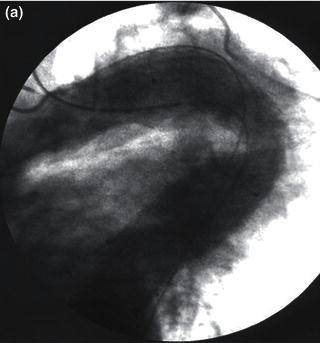

In tortuous aorta, the use of the brachio-femo ral wire may be required to aid advancement and deployment of an endograft. Deployment of an endoluminal graft in a tortuous aorta may be difficult, requiring the use of a brachio-femoral wire (Fig. 1.2). Use of brachio-femoral access wires can help straighten the most angulated of vessels. The presence of a tortuous aorta requires brachio-femoral access to deploy an endoluminal graft (Fig. 1.3). Brachial access is obtained by a percutaneous retrograde puncture of the right brachial artery with an 18 gauge needle or a micropuncture needle. An extra long 450 cm, 0.035 inch angled glide wire is advanced through the brachial sheath into the tortuous thoracic aorta, snared and pulled out through the groin sheath. The technique requires that a protective guiding catheter be placed over the brachial artery to protect the subclavian artery from injury. It is important to have at least a 260 cm long wire and constant tension must be placed on both ends of the wire as the delivery sheath is passed into the aorta [2,3]. By pulling on both ends of the wire an endoluminal graft can be advanced up into the tortuous arch aorta with precise deployment of the endoluminal graft.

Fig. 1.2 (a) Angiogram and (b) illustration demonstrating advancement of a brachio-femoral wire in a tortuous thoracic aorta.

Fig. 1.3 (a) Angiogram and (b) illustration demonstration of deployment of a thoracic endograft using a brachio-femoral wire approach.